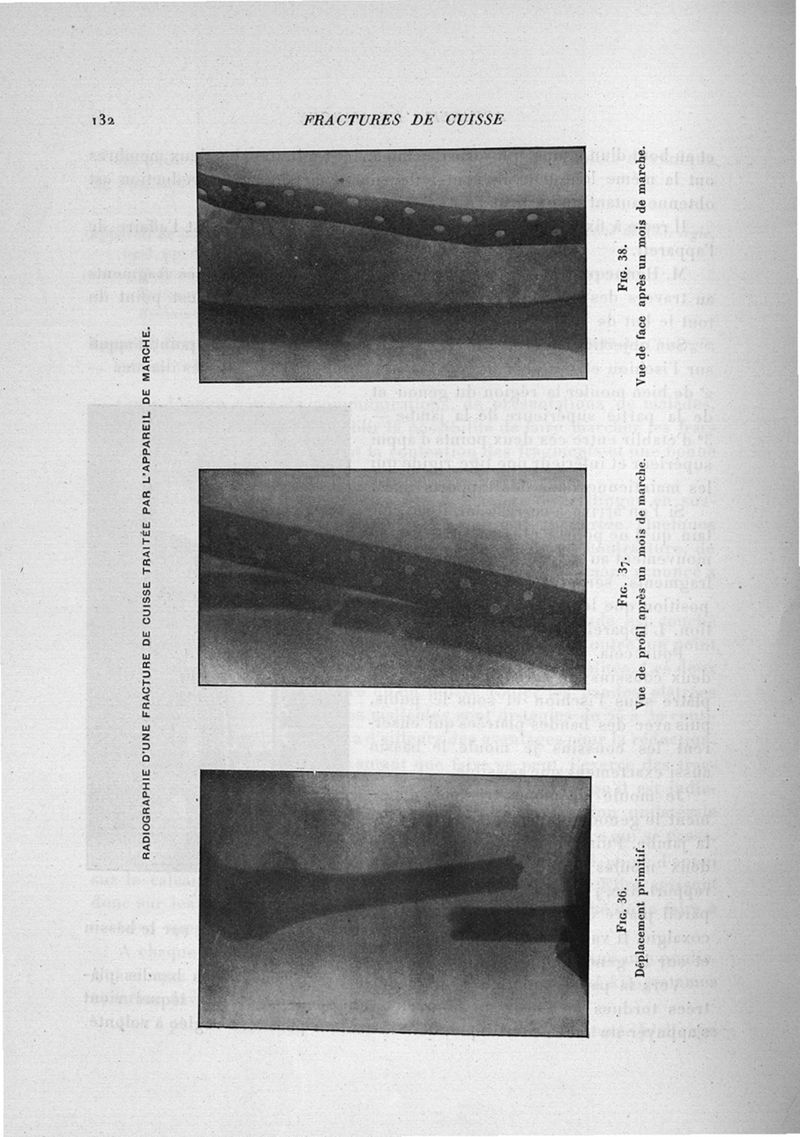

Exposé des travaux scientifiques

Paris, G. Steinheil, 1908.